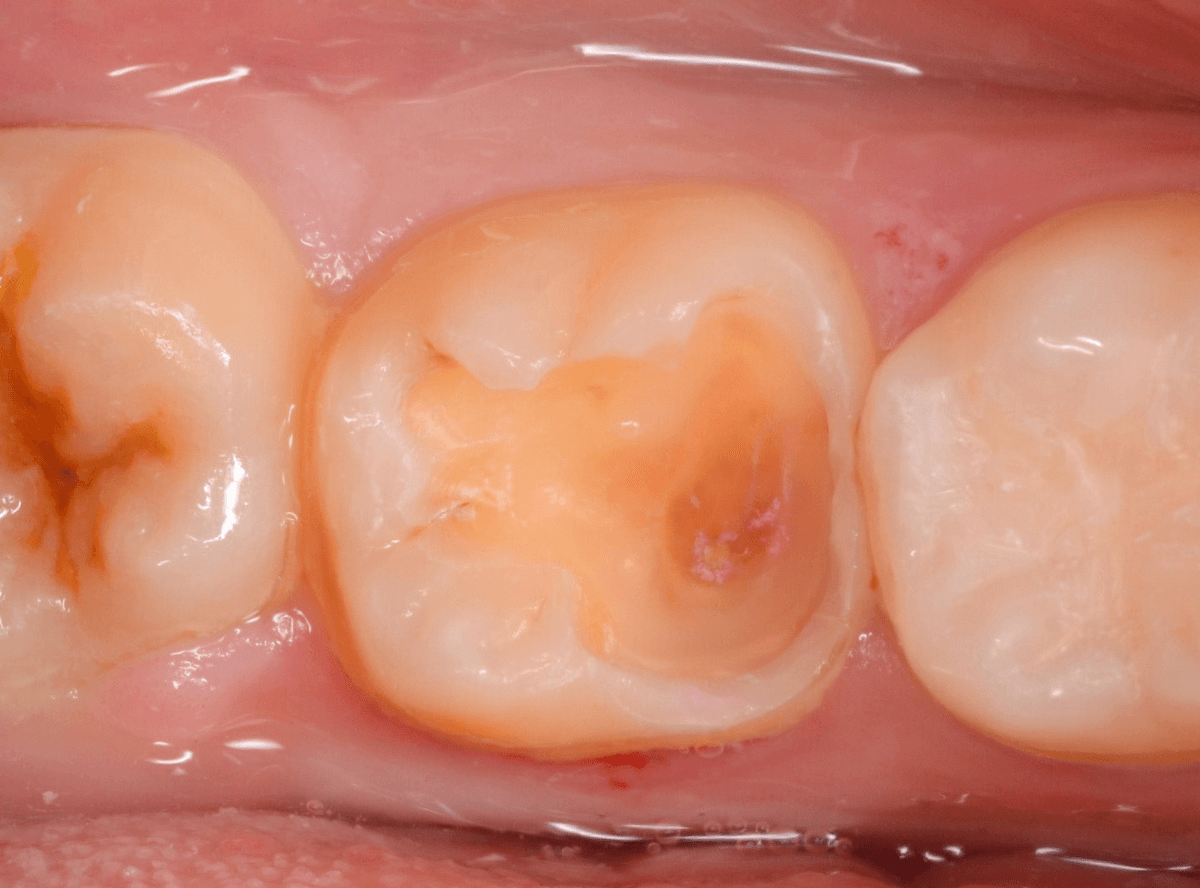

Case.13 問題なさそうなレジンの下で深い虫歯

他の歯の治療希望で来院された患者さんで、レントゲンで大きな虫歯が見つかった方です。

以前に虫歯を削って、レジンをつめる治療がしてあります。

表面を見る限り、特に問題はなさそうです。

まずは、麻酔をしてつめ物を慎重に外してみます。

両歯とも、色々嫌な予感のする所見です。

レジンを除去して虫歯を調べます。

赤い部分が虫歯です。

少しずつ虫歯が出てきました。

慎重にレジンを外して、全ての虫歯を除去しました。

レントゲンから予想される通り、かなり大きな虫歯でした。

症状が出る前に治療が出来て良かったです。